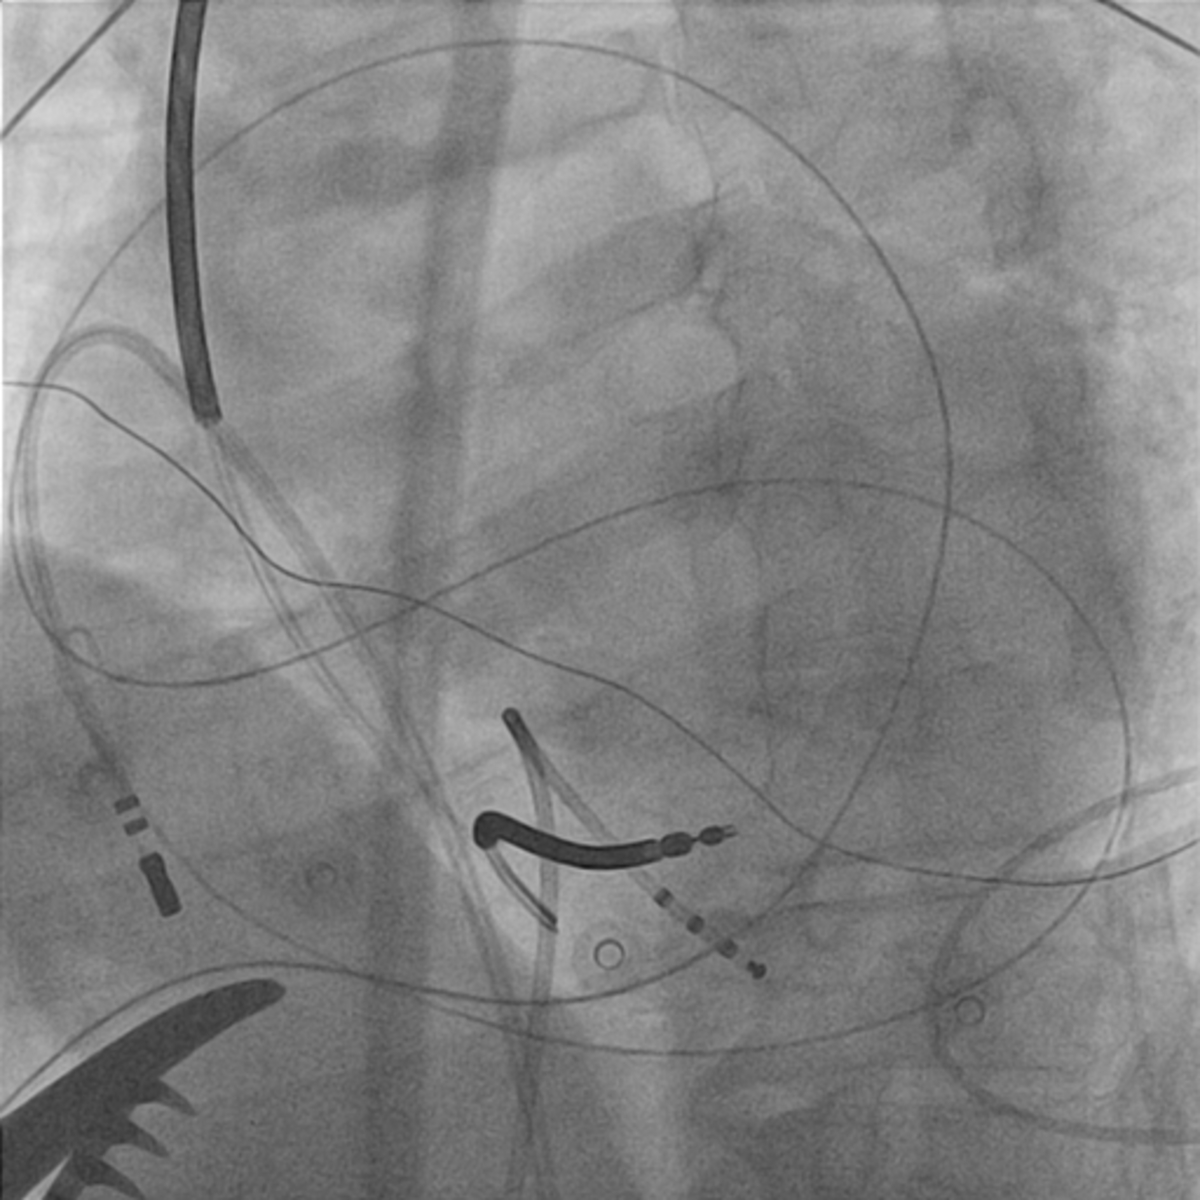

Wire in pericardial space

01_access.jpg